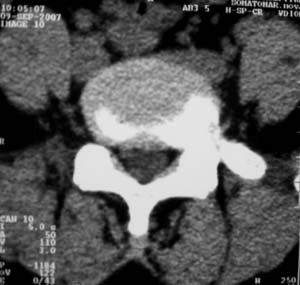

标题: CT9676:女,34岁,腰5骶1右侧神经根增粗?请各位老师会诊! [打印本页]

标题: CT9676:女,34岁,腰5骶1右侧神经根增粗?请各位老师会诊!

女,34岁,腰背部及右下肢酸痛两年余.

神经源性肿瘤可能性大;1椎间孔较对侧明显大,2相应层面似见椎间盘边缘.建议作mri.

神经源性肿瘤?突出?椎间盘扫描的层厚太厚了。建议mri或薄层扫描

对比观察

[emb10]为什么说是椎间盘病变呢?还有椎间盘脱出有脱向头端方向的吗?

腰间盘突出是有的,右侧椎间孔增大,还是做个mri吧。

右侧椎间孔显宽,考虑为体位不对称所致.扫描层厚偏厚了,考虑孔间型间盘突出.